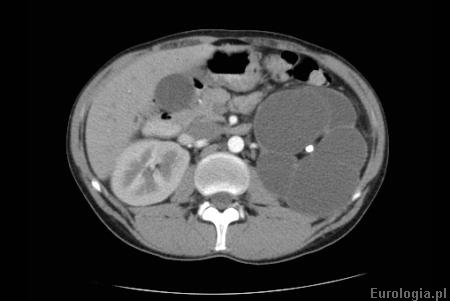

Fot. Wodonercze lewostronne - tomografia komputerowa